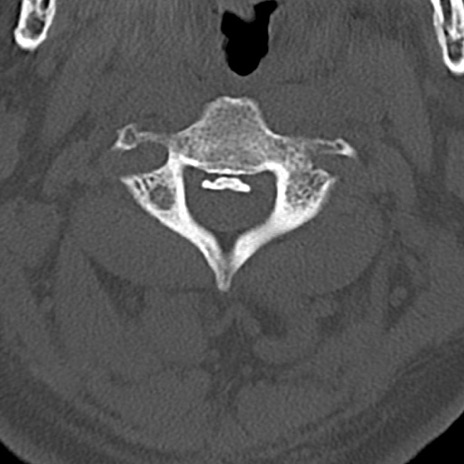

頚椎CT

横断像